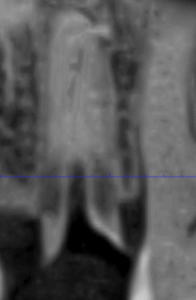

Клинические случаи в эндодонтии